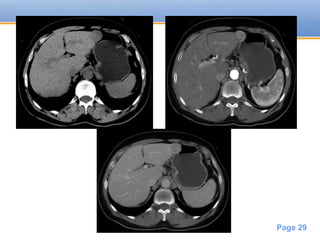

Page 29

• #29 NECT, arterial and portal venous phase in a patient with Hepatitis C with two lesions in the liver (arrows)

• #30 CT scan of the abdomen with quadrephasic liver protocol was performed which confirmed the presence of a hyper-vascular lesion in segment 3, demonstrating washout on portovenous phase.